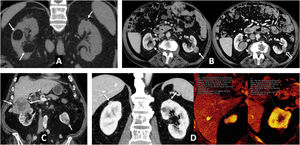

These tumours are more aggressive (often with sarcomatoid features), infiltrating and more prone to venous invasion and distant metastases. They have a worse prognosis and are more radiosensitive (Fig. 4).

Clear cell renal cell carcinomas (ccRCC) with BAP1 somatic mutation. (A) Coronal CT in nephrographic phase. (B, C and D) Axial CT in corticomedullary phase. A 51-year-old woman with constitutional symptoms and a palpable left lumbar mass. CT shows a left renal tumour with highly infiltrative growth and heterogeneous enhancement (arrows), accompanied by a tumour thrombus in the left renal vein (hollow arrows), as well as pulmonary metastases (dashed arrows) and muscle metastases (arrowhead). Histological examination of the surgical specimen showed a histological grade 4 ccRCC with sarcomatoid features and BAP-1 somatic mutation.

Hereditary leiomyomatosis and renal cell carcinoma. A 26-year-old female with constitutional symptoms, pain and a palpable mass in the left lumbar region. (A) MRI. Axial images with T1-weighted, T2-weighted, and parametric map of apparent diffusion coefficient. (B) Coronal non-contrast CT, nephrographic phase and excretory phase. Infiltrating mass measuring 135 mm in the left kidney (arrows). There are extensive cystic-necrotic and haemorrhagic areas (*), the latter with high T1 signal and water diffusion restriction, as well as papillary projections with subtle enhancement on CT, with an increase of between 23 and 31 HU in the nephrographic phase (arrowheads). It is accompanied by a tumour thrombus in the left renal vein, with similar characteristics. (C) Sagittal T2-weighted pelvic MRI performed three years earlier. Uterus with multiple hypointense fibroids (m). (D) Coronal CT image in the nephrographic phase one year after nephrectomy. Recurrence in the form of a heterogeneous mass in the surgical site (r) and liver metastases (dashed arrows). The nephrectomy specimen was initially diagnosed as papillary renal cell carcinoma type 2. Later, loss of FH staining was observed in a controlled immunohistochemical study, allowing for the diagnosis of this specific entity.